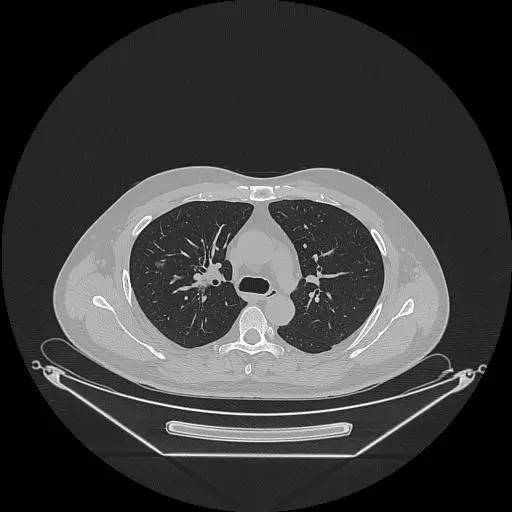

男,47岁,查体发现右肺小结节8月余。

[影像描述]

右肺上叶可见直径约7mm磨玻璃样结节,其内见空泡影,有浅分叶及血管集束征象,增强扫描无强化,余肺、纵隔未见明显异常。

右肺上叶不典型腺瘤样增生(AAH)

AAH的影像学特点为呈类圆形小病灶,边界清楚,淡至中等密度均匀的毛玻璃或磨砂玻璃阴影,不遮蔽其下的肺实质,多数在5 mm以下。